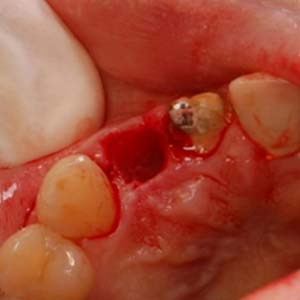

拔除殘留牙根

測量角度與深度

置入適當位置

骨缺損處,置放骨粉

當日在拔除牙齒後,立即在拔牙窩洞裡,置入適當尺寸的植體,並在使用人工骨粉填塞縫隙。

置入植牙